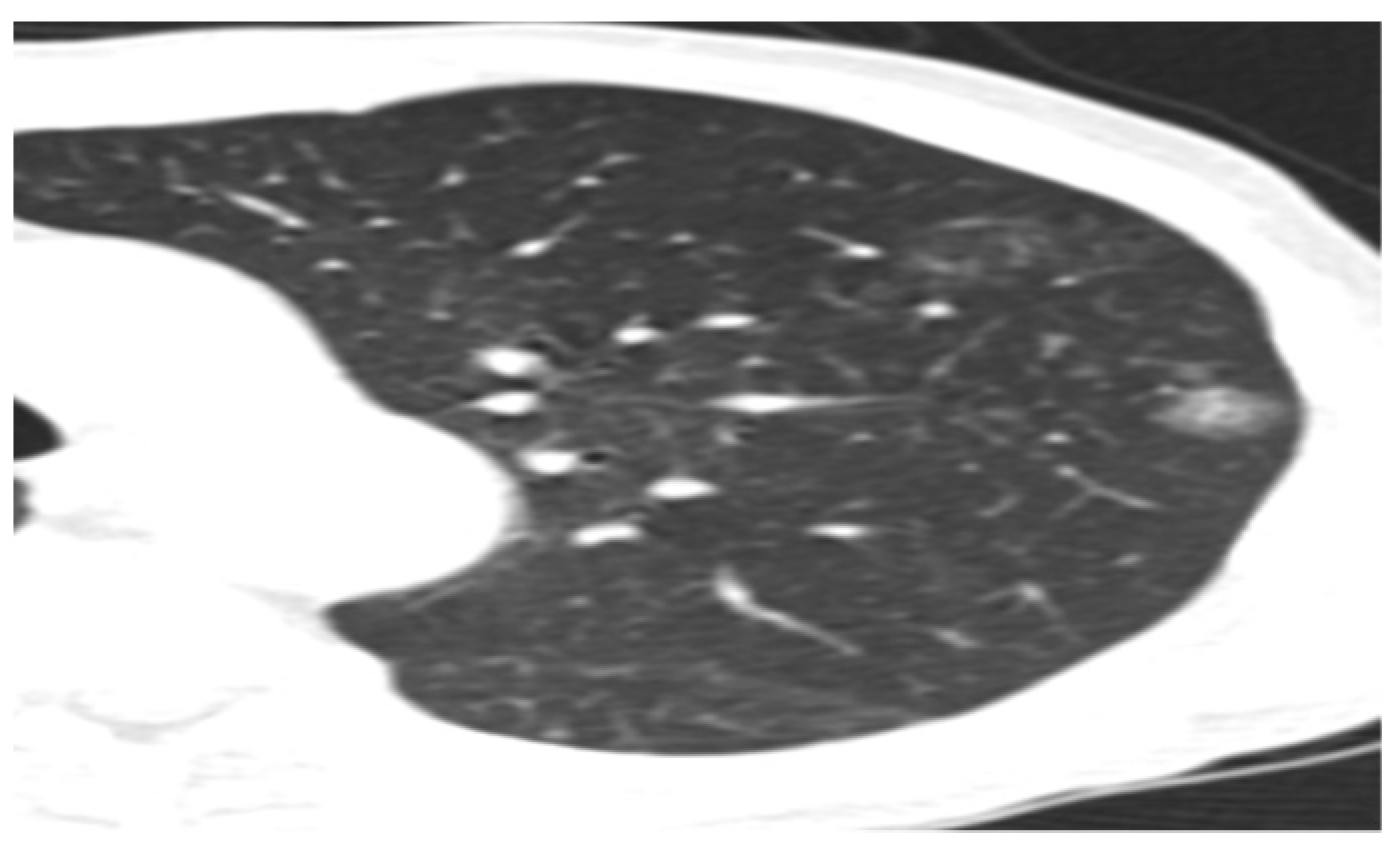

3. Results